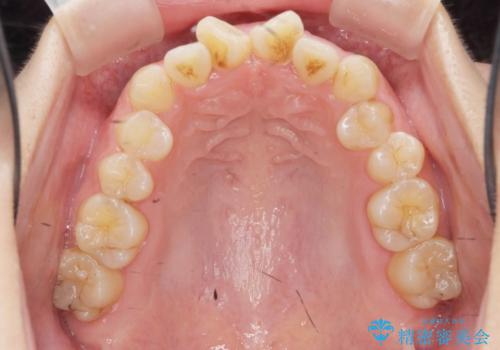

上下の歯のがたつきを改善するマウスピース矯正治療と、下顎に見られる大きな骨隆起を外科的に除去する治療計画を進めていきます。

歯並びが改善したとともに、骨隆起を除去したことで舌をしまうスペースも増え安定した口腔内環境を確立することができました。